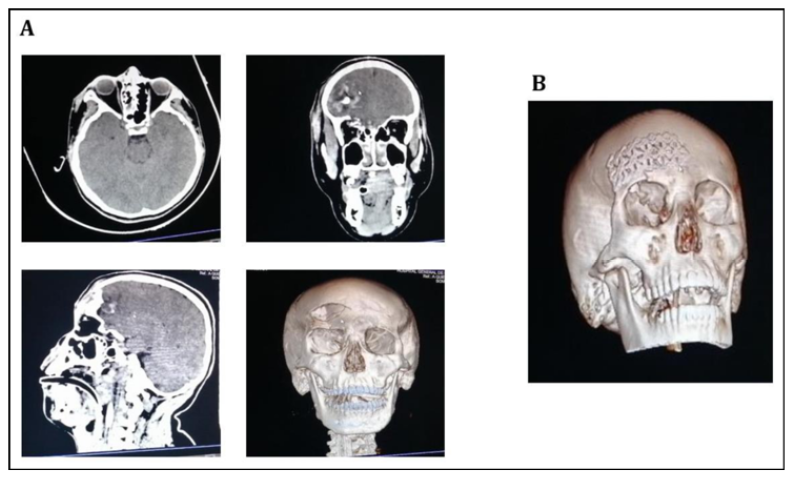

Post Traumatic Inferior Labial Artery Pseudoaneurysm After Lip Laceration: Case Report

Napasorn Phutong, Weeravit Ruangsirinusorn and David Limkul. 12(4): 65-67.